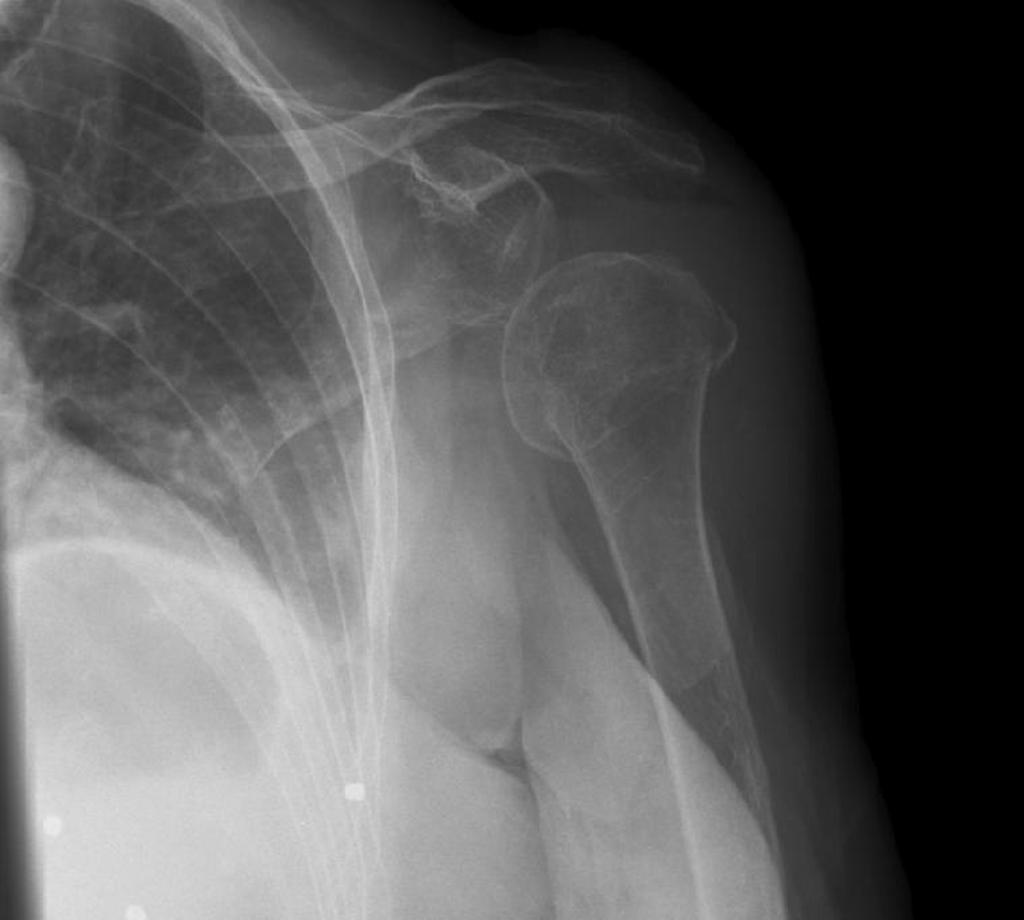

pseudosubluxation secondary to lipohaemarthrosis; hover to reveal annotations

'Pseudosubluxation' in the context of shoulder imaging refers to apparent incongruity of the glenohumeral joint secondary to a pathological process (such as effusion) mimicking a true dislocation.

While reporting, the shortest distance between the cortical bone of the inferior aspect of the acromion process and the cortex of the superior humeral head is measured; this is known as the acromiohumeral interval. This measurement relies on a reasonably standard AP projection of the shoulder – lower centred examinations of the humerus may artificially reduce this interval due to the divergent beam. An acromiohumeral interval of greater than 12mm indicates inferior subluxation of the humeral head and should raise the possibility of an effusion.